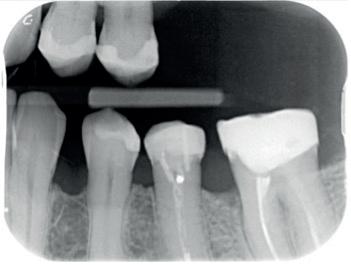

Een 62-jarige man hield in de nazorgfase een pocket van 8 mm met bloeding na sonderen mesiaal van de 36 ondanks 3-maandelijkse recall (afbeelding 2.1 en 2.3). De mondhygiëne was matig en plaque was aanwezig. Chirurgie werd geadviseerd, maar de pa-

tiënt wees dit af. Ook hier werd de pocket behandeld onder anaesthesie. De natriumhypochloriet/aminozuur-gel werd viermaal aangebracht, telkens gevolgd door ultrasone en handinstrumentatie. Tot slot werd cross-linked hyaluronzuur ingebracht. De mondhygiëne werd bijgestuurd en meneer werd gemotiveerd dagelijks interdentale ragers te gebruiken naast het poetsen.

Na zes maanden was de pocketdiepte teruggebracht tot 3 mm en was er geen bloeding na sonderen (afbeelding 2.2 en 2.4).